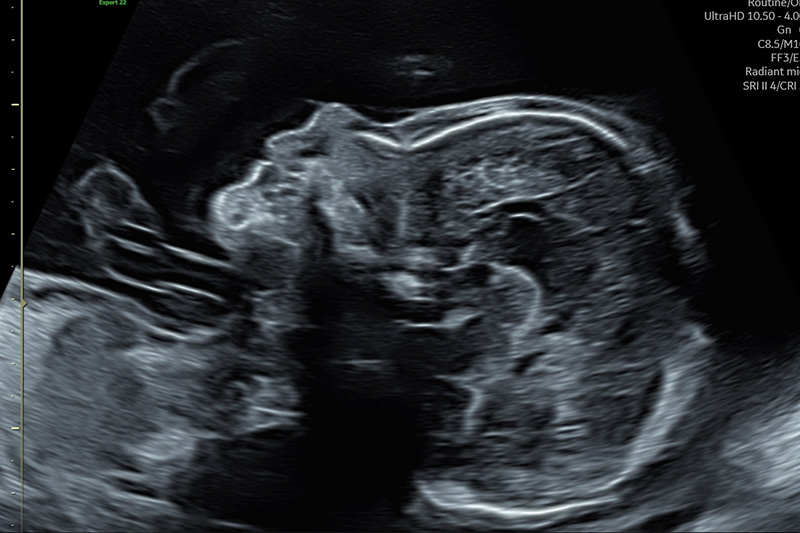

Ultraschall -Feindiagnostik, erweitertes Organscreening

Der beste Zeitpunkt ist die 20.-22. Woche der Schwangerschaft.

Ziel dieser Untersuchung

ist es, Informationen über die Schwangerschaft und den Zustand des ungeborenen Kindes zu erhalten. Es werden die einsehbaren Organe (Gehirn, Herz, Nieren, Wirbelsäule, Extremitäten, ...) hinsichtlich ihrer korrekten Ausbildung und zeitgerechten Entwicklung untersucht.

So können häufig Gefährdungen des ungeborenen Kindes frühzeitig erkannt werden, und es kann eventuell hilfreich eingegriffen werden:

• beispielsweise durch eine Behandlung des Kindes intrauterin (Verschluss eines offenen Rückens, Erweiterung verengter kindlicher Herzklappen, …)

• die Vorbereitung einer Behandlung nach der Geburt (z.B. bei bestimmten Herzfehlern), oder die Planung von Geburtsart (Spontangeburt oder Kaiserschnitt), Geburtsort (Kinderklinik ja/nein) und Geburtszeitpunkt.

• Eine große Zahl von Fehlbildungen kann heute mit Ultraschall ausgeschlossen werden.

Wichtiger Bestandteil der Ultraschalluntersuchung ist auch die Überprüfung der Durchblutung der Gebärmutter und der Nabelschnur (Doppler-Sonografie). Hier können entscheidende Informationen über ein erhöhtes Risiko für Probleme gefunden werden, die im letzten Drittel der Schwangerschaft auftreten (z.B. für eine Mangelversorgung des Kindes über die Placenta oder eine Erkrankung der Mutter durch Bluthochdruck und damit verbundene Risiken).